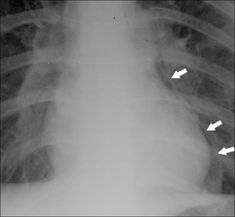

image

Figure 27.4 Young male. Recent vomiting episode. Now complains of chest pain. Air is present in the mediastinum (arrows). Oesophageal rupture. Boerhaave’s syndrome.